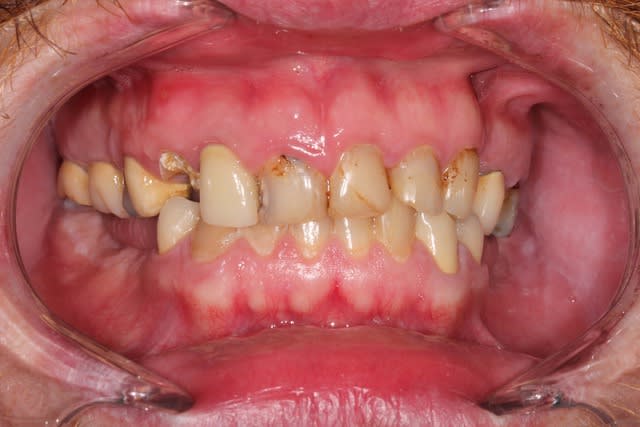

Patient, une trentaine d'années, état bucco-dentaire désastreux.

Le patient porte un stellite en bas. Il souhaite une réhabilitation fixe au maxillaire. J'ai bien un avis mais j'aimerais connaître le votre.

13/14/25 sont mobiles

Ci-joint pano et photo.